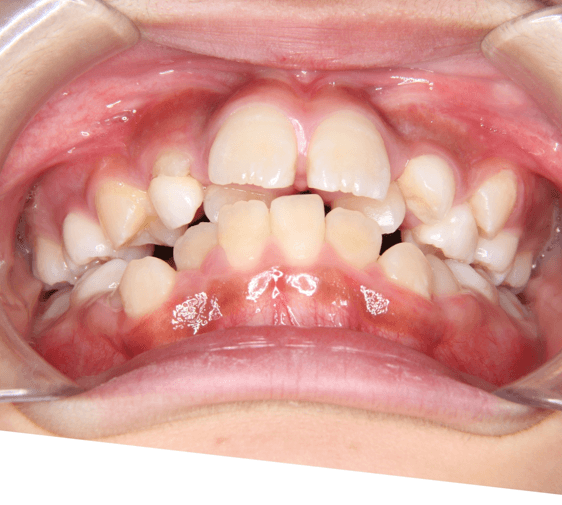

| 年齢・性別 | 7歳1ヶ月の男児 |

|---|---|

| 主訴 | 歯の生えるスペース不足が懸念され、歯列の乱れ(叢生)を整えるために来院された患者様です。 |

| 治療期間・回数 | 1年3ヶ月・11回 |

| 費用 | 420,000円(税別) |